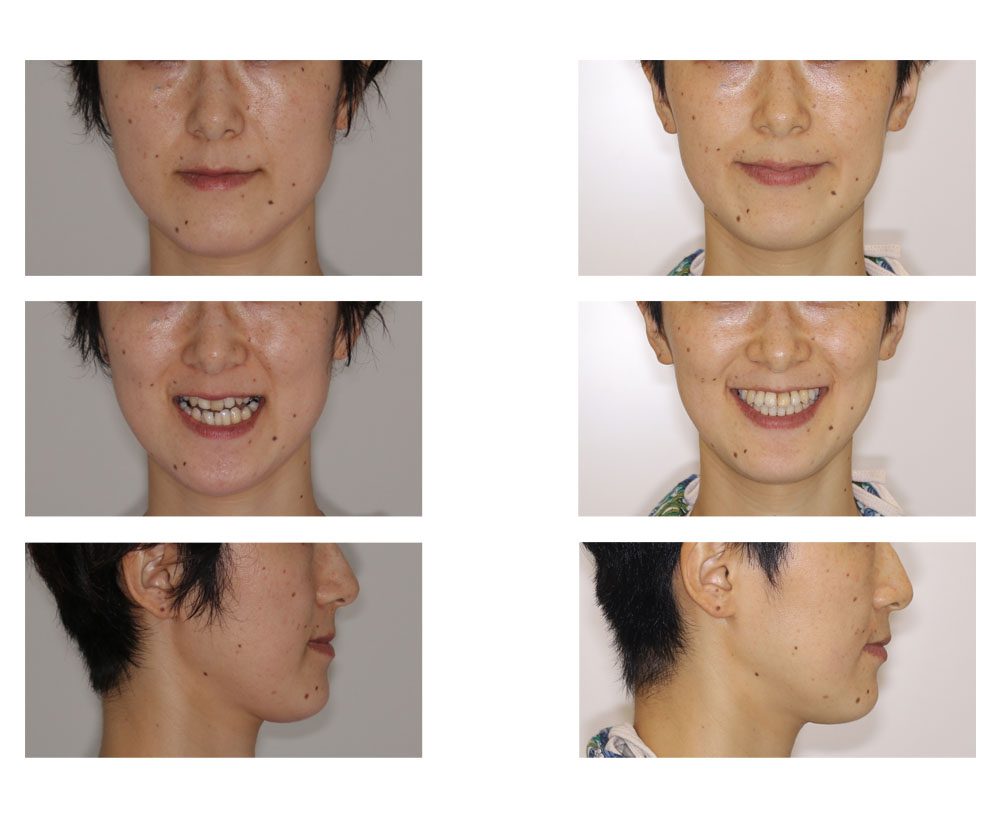

品質一番の 下顎前突(反対咬合) 奈良市の矯正歯科「氏井矯正歯科 | 歯科学